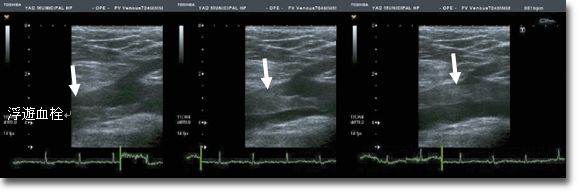

下肢静脈エコー

下肢静脈エコーには血栓評価と静脈瘤評価があります。足のむくみ(腫れ)は下肢静脈内に血栓が存在している可能性があり、放置していると肺梗塞という非常に危険な状態に陥る可能性があります。エコーによる早期の発見、早期の処置が必要と考えられます。下肢静脈瘤検査では瘤の有無や瘤内血栓の存在、静脈瘤の原因とされる静脈弁逆流を評価します。検査時間は20分~40分程度です。